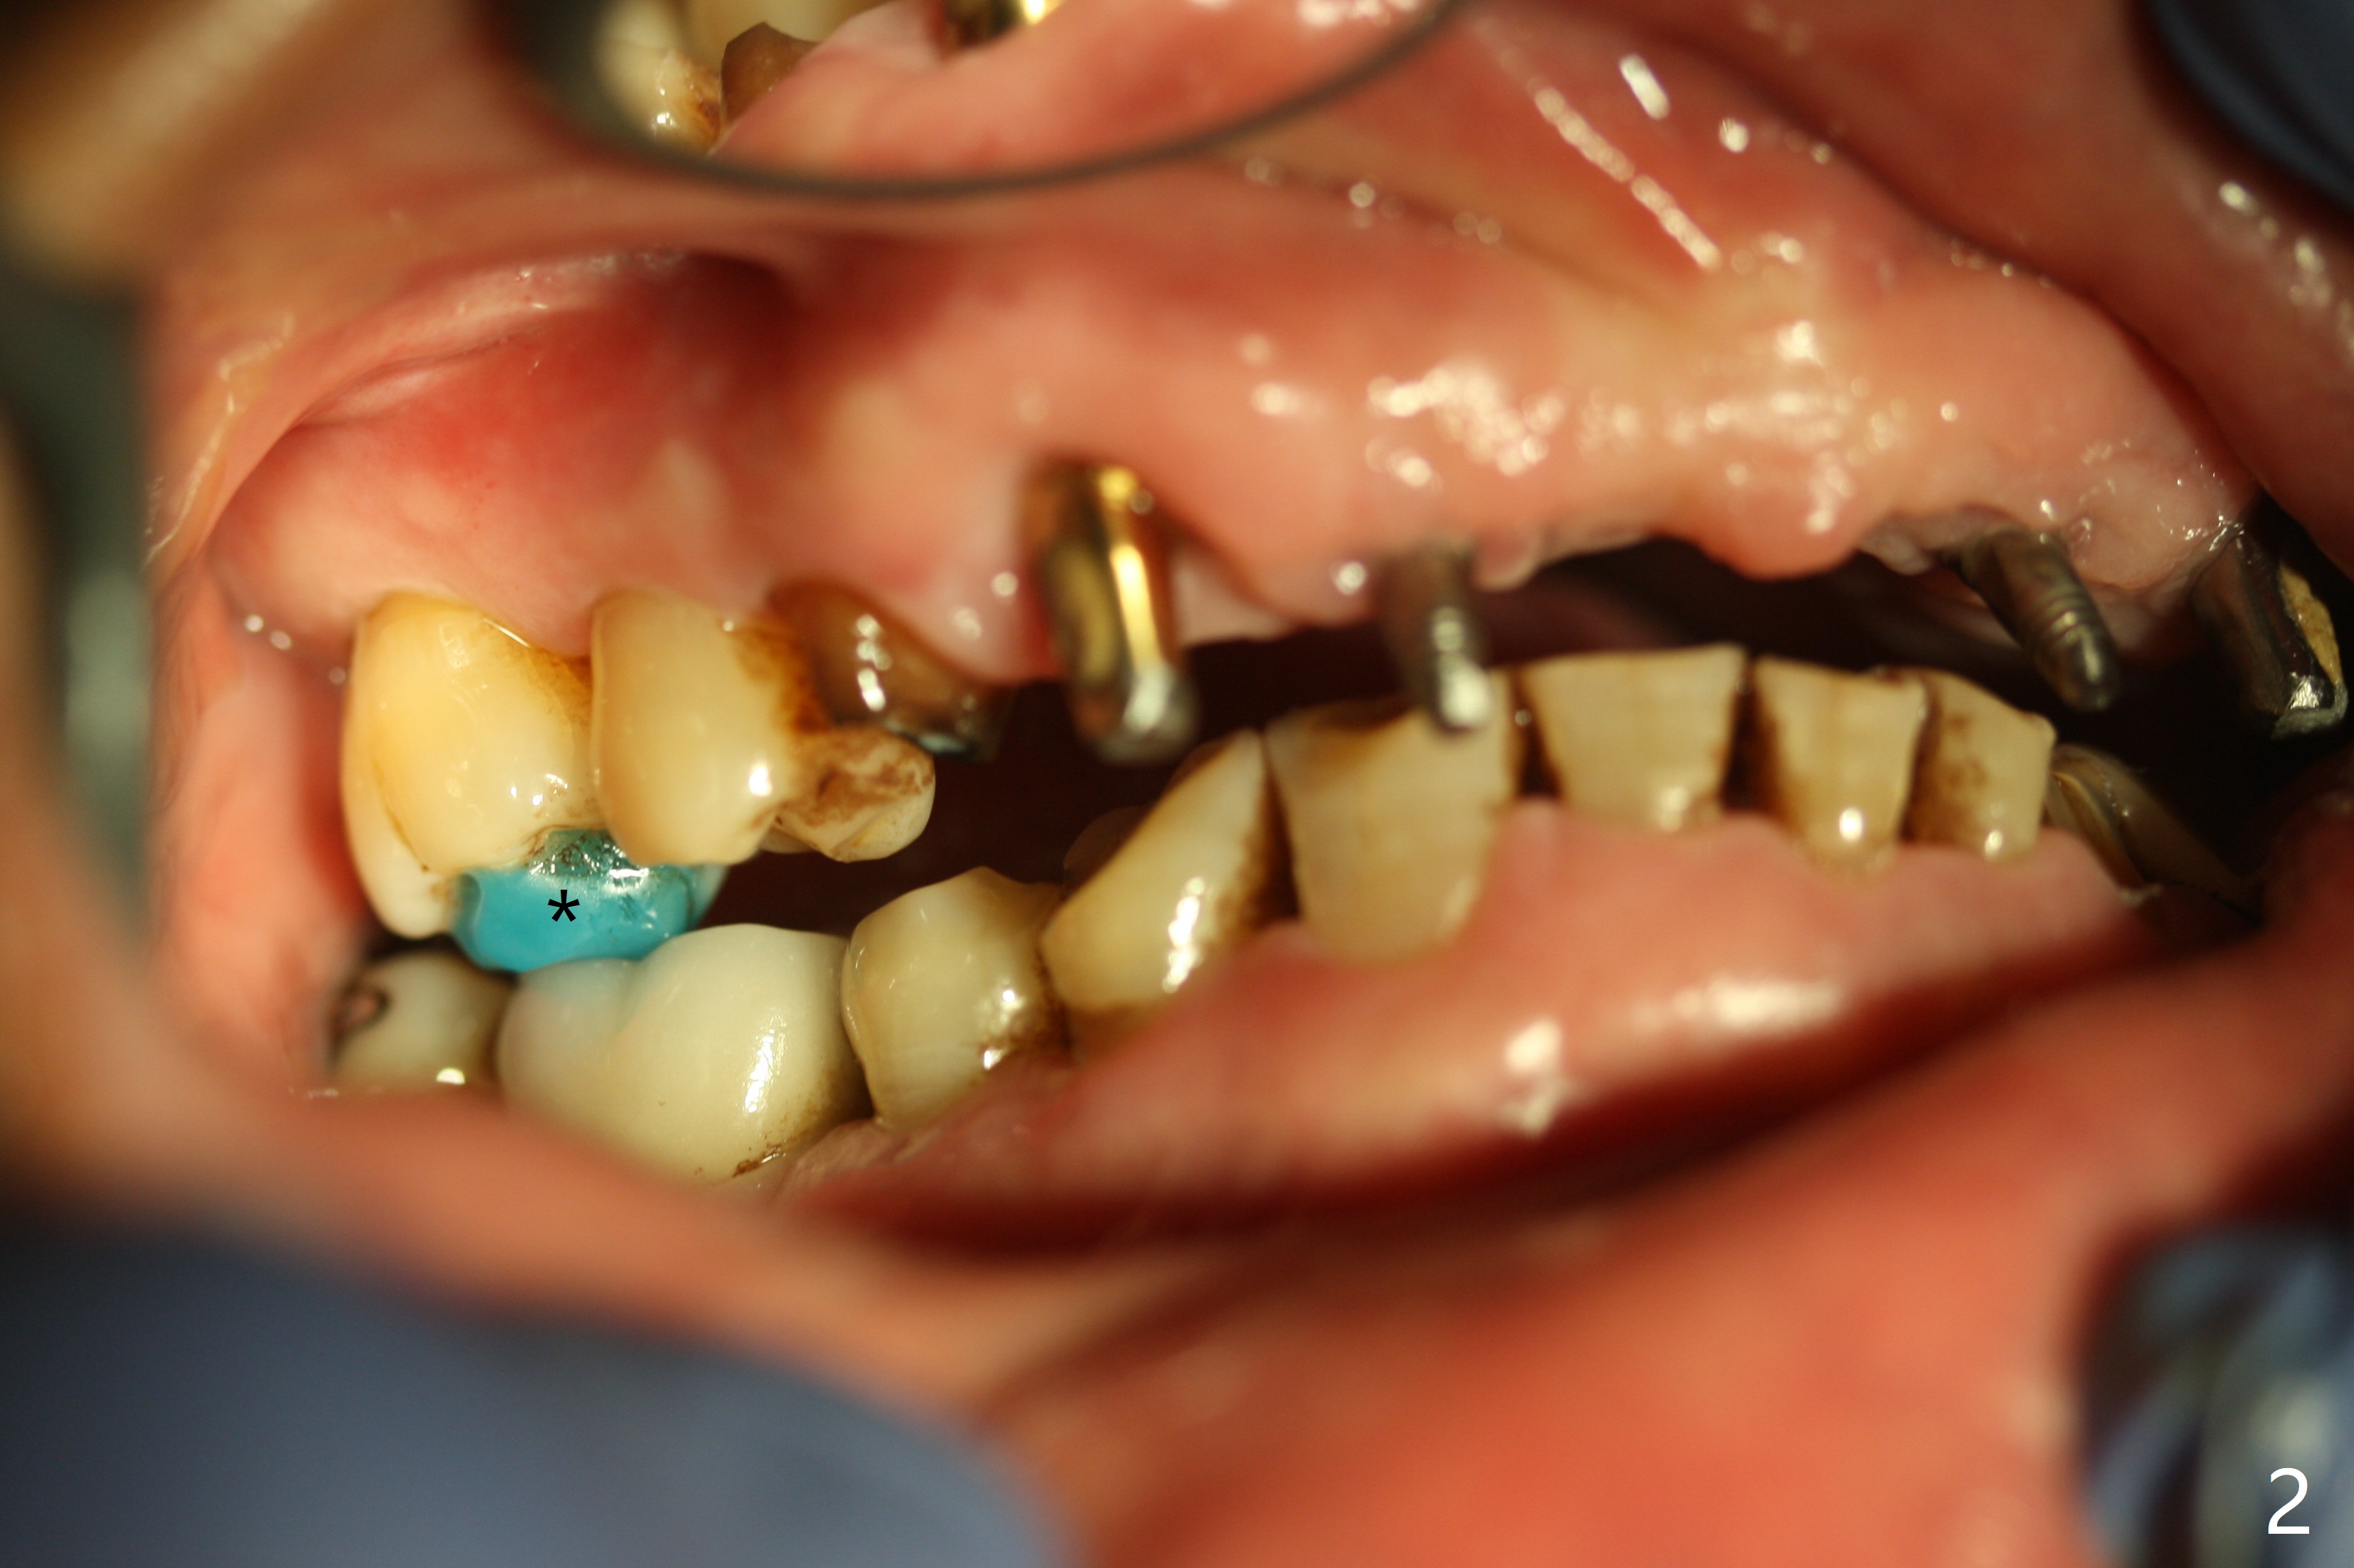

To have enough clearance for the splinted provisional at #6-12 (Fig.1 *), composite has been placed in the posterior teeth (bilateral, *, Fig.2). When the composite is removed, there is no clearance between the implants/abutments of #7 or 10 (Fig.3). Incision is made with removal of the 1-piece implant at #7; there is enough bone to move the osteotomy buccal (Fig.4 arrowhead). When the same implant is placed buccal (Fig.5), there is sufficient clearance for restoration (Fig.6 *), while there is still enough buccal bone left (Fig.7). When the patient returns 5.5 (for #7 and 10)/6.5 (#6,11,12) months postop, his chief complaint is tenderness lingual to #11. In fact, the abutment screw is loose at #11, while the implant at #10 has mobility (Fig.8), which is related to loss of the posterior stops (*) due to wear. There is slight bone loss mesial to #10 implant 5.5 months postop (Fig.10, as compared Fig.9). CBCT taken 5.5/6.5 months postop shows no bone loss (Fig.11-15). The 3x14 mm 1-piece implant at #10 is mobile 9 months postop and is removed and replaced by a 3.5x13 mm 2-piece one with slightly buccal osteotomy (Fig.16). PAs are taken prior to impression (Fig.17,18). The abutment at #12 is loose (<). More composite needs to be added to the occlusal surface of the upper posterior teeth. Finally the patient agrees to have crowns for the upper posterior teeth.